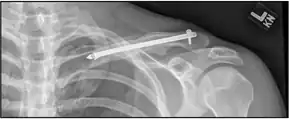

X-ray of the above comminuted fracture treated with an intramedullary fixation device

For breaks in the middle of the clavicle in children surgery resulted in faster recover but more complications.[11] The evidence for different types of surgery for breaks of the middle part of the clavicle is poor as of 2015.[12]

A discontinuity in the bone shape often results from a clavicular fracture, visible through the skin, if not treated with surgery. Surgical procedures often call for open reduction internal [plate] fixation where an anatomically shaped titanium or steel plate is affixed along the superior aspect of the bone by several screws. In some cases, the plate is removed after healing due to discomfort, to avoid tissue aggravation, osteolysis or subacromial impingement. This is especially important with a special type of fixation plate called hook plate.[14] With anatomical plates plate removal is considered an elective procedure that is rarely necessary. An alternative to plate fixation is elastic TEN intramedullary nailing. These devices are implanted within the clavicle's canal to support the bone from the inside. Typical surgical complications are infection, neurological symptoms distal the incision (sometimes to the extremity), and nonunion of the bone (failure of the bone to properly fuse together).